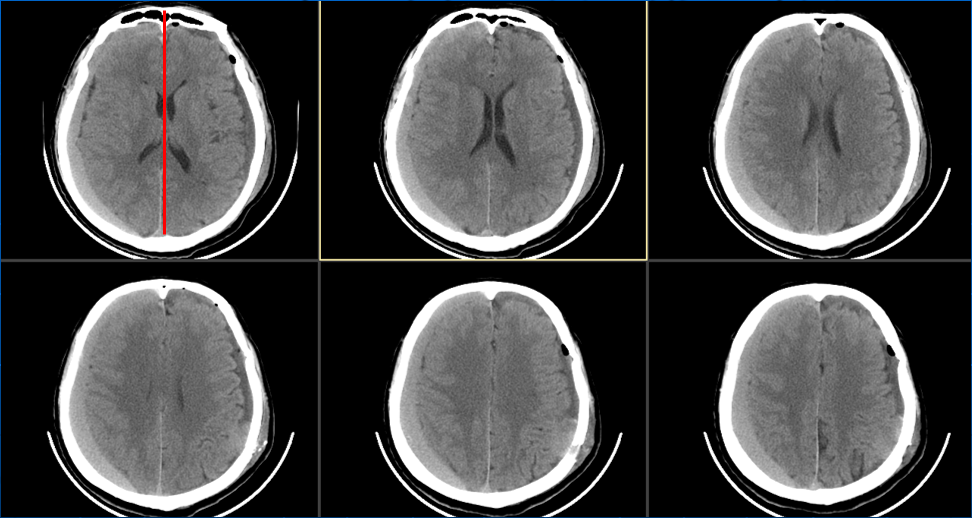

患者约2个月前无明显诱因(否认外伤史)间断出现头痛,头痛为胀痛,左侧较明显,恶心未吐,食欲、睡眠尚可,未予特殊诊治,1个月前患者头痛逐渐加重,思睡,反应略迟钝,行头部CT检查示“慢性硬膜下血肿(双侧)”,于2018年12月15日行颅骨钻孔引流术(左)。术后9天患者恢复良好出院。出院后2周于2019年1月9日患者头痛再次加重,伴有反应迟钝,走路困难,疲乏无力再次就诊,头部CT示“慢性硬膜下血肿(右侧)”,当日再次行颅骨钻孔引流术(右)。术后患者一般状态逐渐好转,无抽搐,无尿便失禁。

术后当日(2019年1月16日)

术后3天(2019年1月18日)

2. 与SDH 疾病本身相关因素,如巨大血肿、双侧血肿、血肿腔内有分隔、血肿机化、CT 表现为高/混杂密度;

血肿分隔多房。

脑萎缩较明显。

存在分隔。

双侧血肿,量较大。